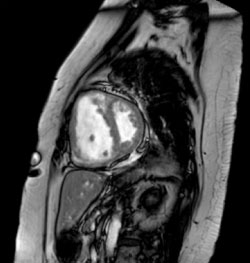

My primary T32 project focused on the use of cardiac magnetic resonance (CMR) for assessment of myocardial disease in patients with pulmonary hypertension under the mentorship of Dr. Karen Ordovas. A limitation of the current management of patients with pulmonary hypertension is the requirement for invasive cardiac catheterization. CMR imaging allows noninvasive evaluation of cardiac structure and function, and therefore may be a useful tool for evaluation of myocardial dysfunction in this patient population. The preliminary results of my T32 project were presented at the Society of Thoracic Radiology annual meeting, the Association of University Radiologists Research Scholar program, and have been submitted for publication.

Figure: Sagittal Steady State Free Precession CMR in a patient with pulmonary hypertension.